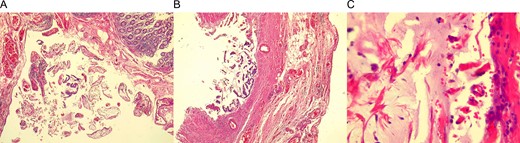

Pathology described a low grade disseminated mucinous cystadenoma of the appendix, the serosa of the cecum was congestive and infiltrated with mucous material (Fig. 3A), the base of the appendix was perforated (Fig. 3B) and was covered with mucous-hemorrhagic material (Fig. 3C). Pseudomyxoma peritonei was the final diagnosis.

(A) Cecum wall, congestive and infiltrated with mucous material. (B) Appendix base, with atypia of goblet cells. (C) Mucous material covering the appendix base.